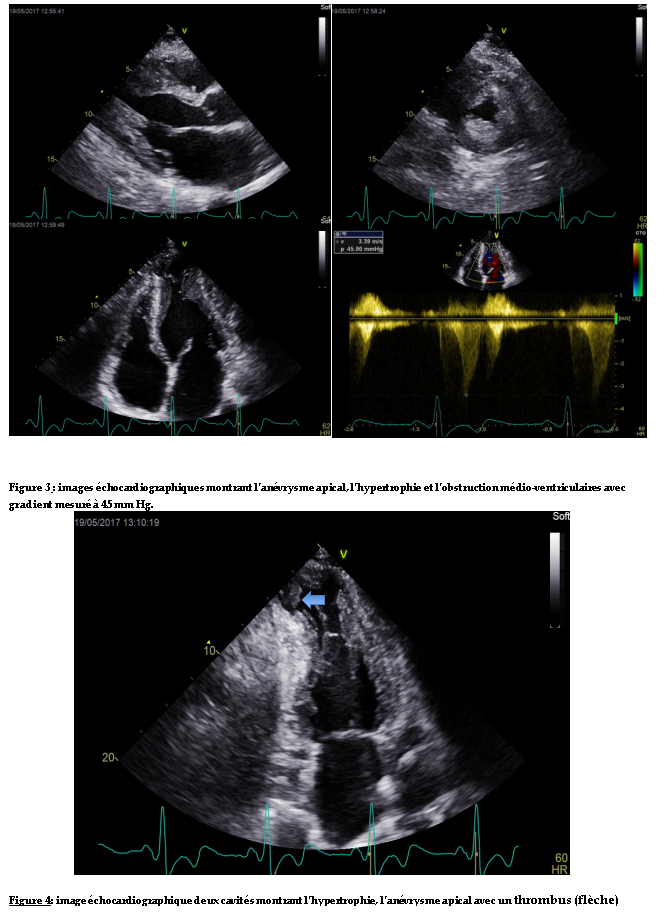

L’échocardiographie Doppler mettait en évidence une hypertrophie pariétale du ventricule gauche asymétrique définissant une cardiomyopathie hypertrophie type III de Maron. Elle était plus importante au niveau médian (mesurée au maximum à 26 mm). Il y avait une accélération importante du flux au niveau médio-ventriculaire suggérant une obstruction qui était confirmée au Doppler continu. Le gradient maximal était en effet de 45 mm Hg (figure 3). Il y avait une déformation anévrysmale de l’apex associée à un thrombus enclavé et peu mobile (figure 3,4). Il y avait une fuite mitrale moyenne (VR=32 ml). L’oreillette gauche était dilatée, il y avait une dysfonction diastolique importante avec un profil mitral restrictif.

Observation : Nous rapportons le cas d’un sujet de 50 ans, reçu pour des palpitations hyperkinétiques,de début brutal, durant une demi-heure environ et répétitives. L’examen clinique à l’admission révélait une tachycardie régulière sans signe d’insuffisance cardiaque. L’électrocardiogramme inscrivait une tachycardie régulière à QRS larges, monomorphes avec un aspect sinusoïdal et une fréquence à 300 cycles par minute. Une cardioversion électrique à 300 joules avait été effectuée avec obtention d’une activité sinusale à l’ECG. L’échocardiographie Doppler mettait en évidence une hypertrophie pariétale du ventricule gauche asymétrique localisée au niveau médian et mesurée au maximum à 26 mm. Il y avait une accélération importante du flux au niveau médio-ventriculaire suggérant une obstruction qui était confirmée au Doppler continu. Le gradient maximal était en effet de 45 mm Hg. Il y avait une déformation anévrysmale de l’apex associée à un thrombus enclavé et peu mobile. L’évolution avait été marquée par des épisodes brefs de tachycardie ventriculaire. Le patient avait reçu,par la suite, une dose de charge d’amiodarone avec une stabilité sur le plan rythmique. Un traitement bétabloquant était entrepris associé à un diurétique et à un anti-vitamine K.

Doppler echocardiography revealing a parietal hypertrophy of the asymmetric left ventricle located at the median level and measured to a maximum of 26 mm. There was significant acceleration of the flow at the mid-ventricular level suggesting an obstruction that was confirmed to continuous Doppler. The maximum gradient was 45 mm Hg. There was aneurysmal deformation of the apex associated with a thrombus that was enclosed and not very mobile. Evolution had been marked by brief episodes of ventricular tachycardia. The patient subsequently received a dose of amiodarone loading with rhythmic stability. Beta blocker was initiated with a diuretic and anti-vitamin K.